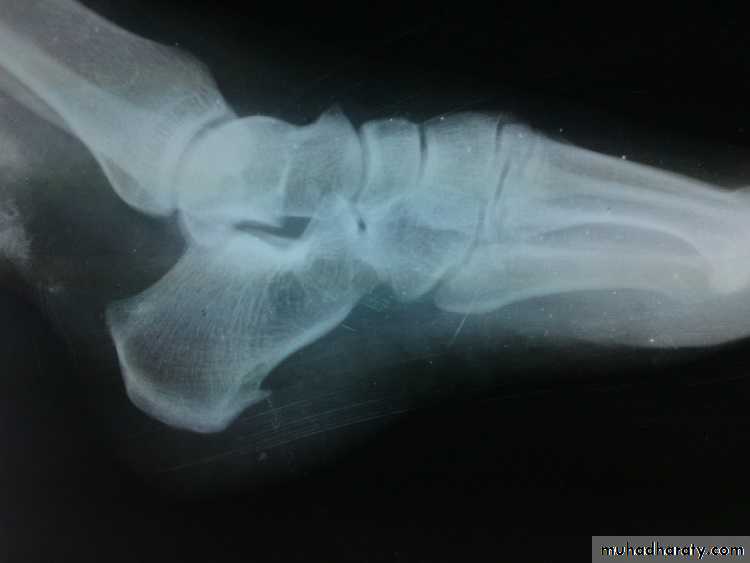

Rigid club foot